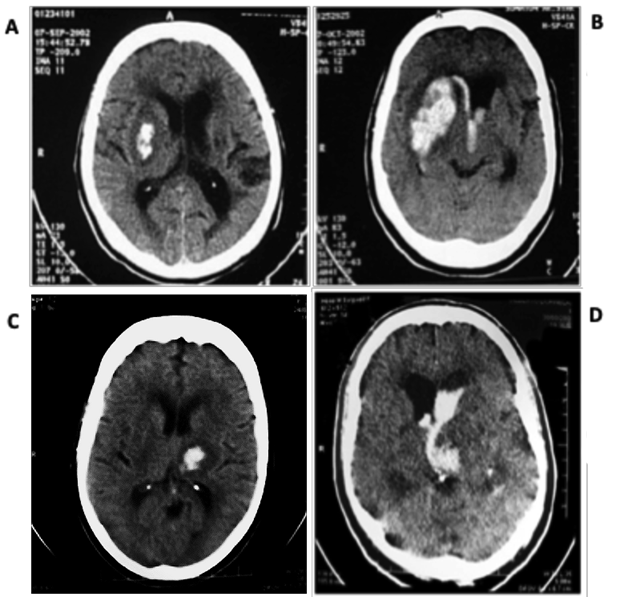

As for the clinical-neurological picture, the main findings were Motor deficit in 46% of patients (n=245), lowered level of consciousness in 38% (n=201), 17% with GCS-P between 09-12 (n=92), 18% with GCS-P 04-08 (n=93) and 3% with GCS-P ≤ 3 (n = 16). Regarding the distribution of cases according to the topography of the PICH we observed that they had hemoventricular 40% of patients (n=212), lobar lesions 34% patients (n=183), lesions in deep base nucleus topography 14% of patients (n=75) and thalamic hematomas 12% of patients (n=62). Regarding the volume of the lesions, on the other hand, the most observed range, in 49% of patients (n=263), was ≤ 30ml, followed by lesions between 31-50ml, in 25% of cases (n=148) and finally lesions ≥ 51ml in 23% of cases (n=121) (Table 2). Respective examples in Figure 1.

Figure 1 Examples of PICH extracted from the case series of this article, classified by skull CT, as to topography and volume of the lesion, except for ventricular lesions.